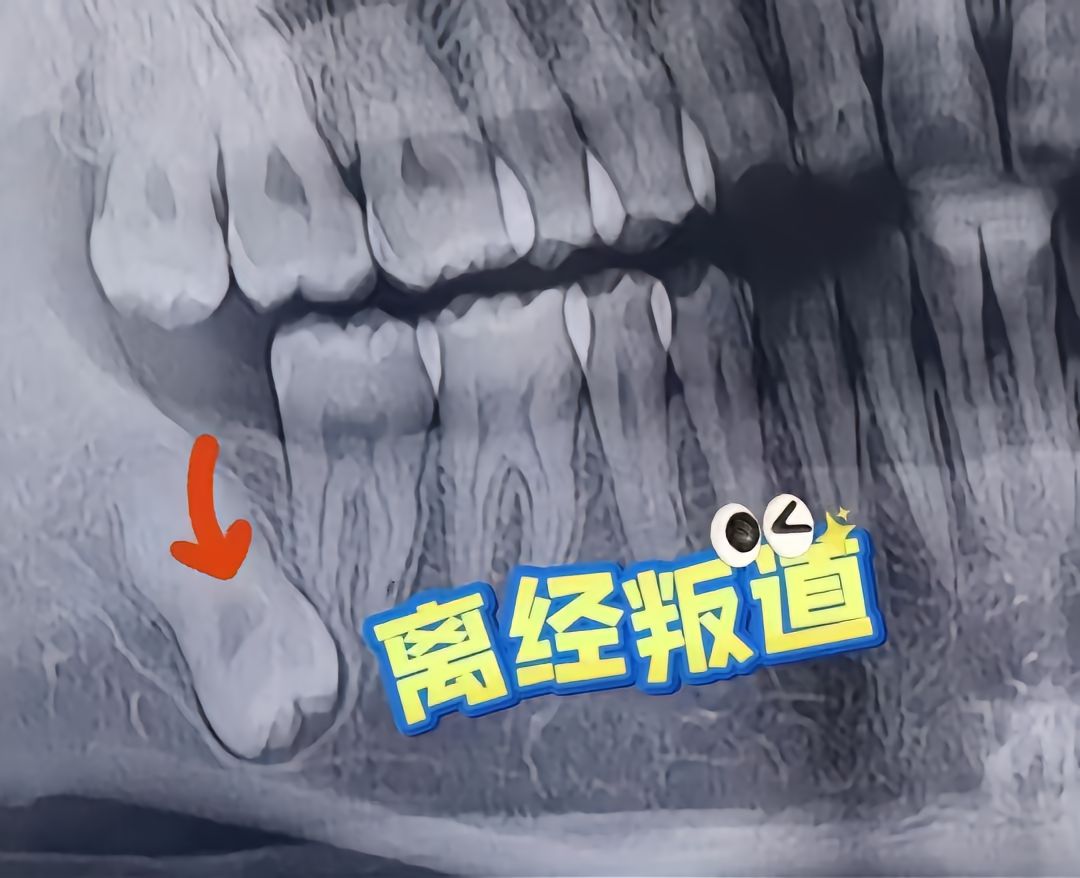

各种各样生长的牙齿